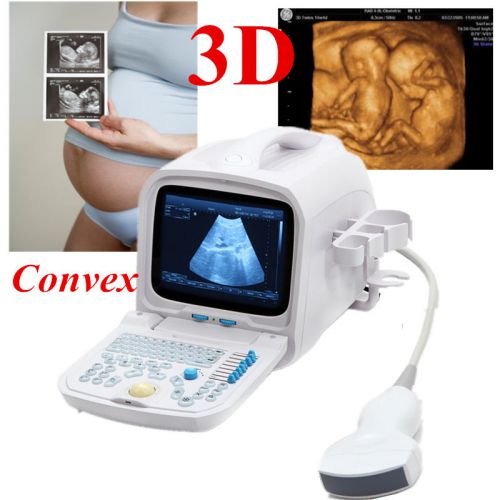

3D PC FULL digital Portable ultrasound scanner machine 3.5mhz Convex 3Y WARRANTY

Internal 3D 3.5mhz convex+6.5mh Transvaginal Portable Ultrasound Scanner machine